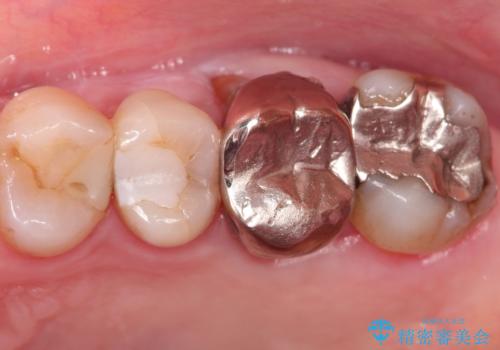

根管治療から被せもの治療(ベレッツァ)まで行いました。(根管治療は林院長に依頼)

妥協せずにすべての治療を行うことで最終的な被せものの適合を高める事ができます。